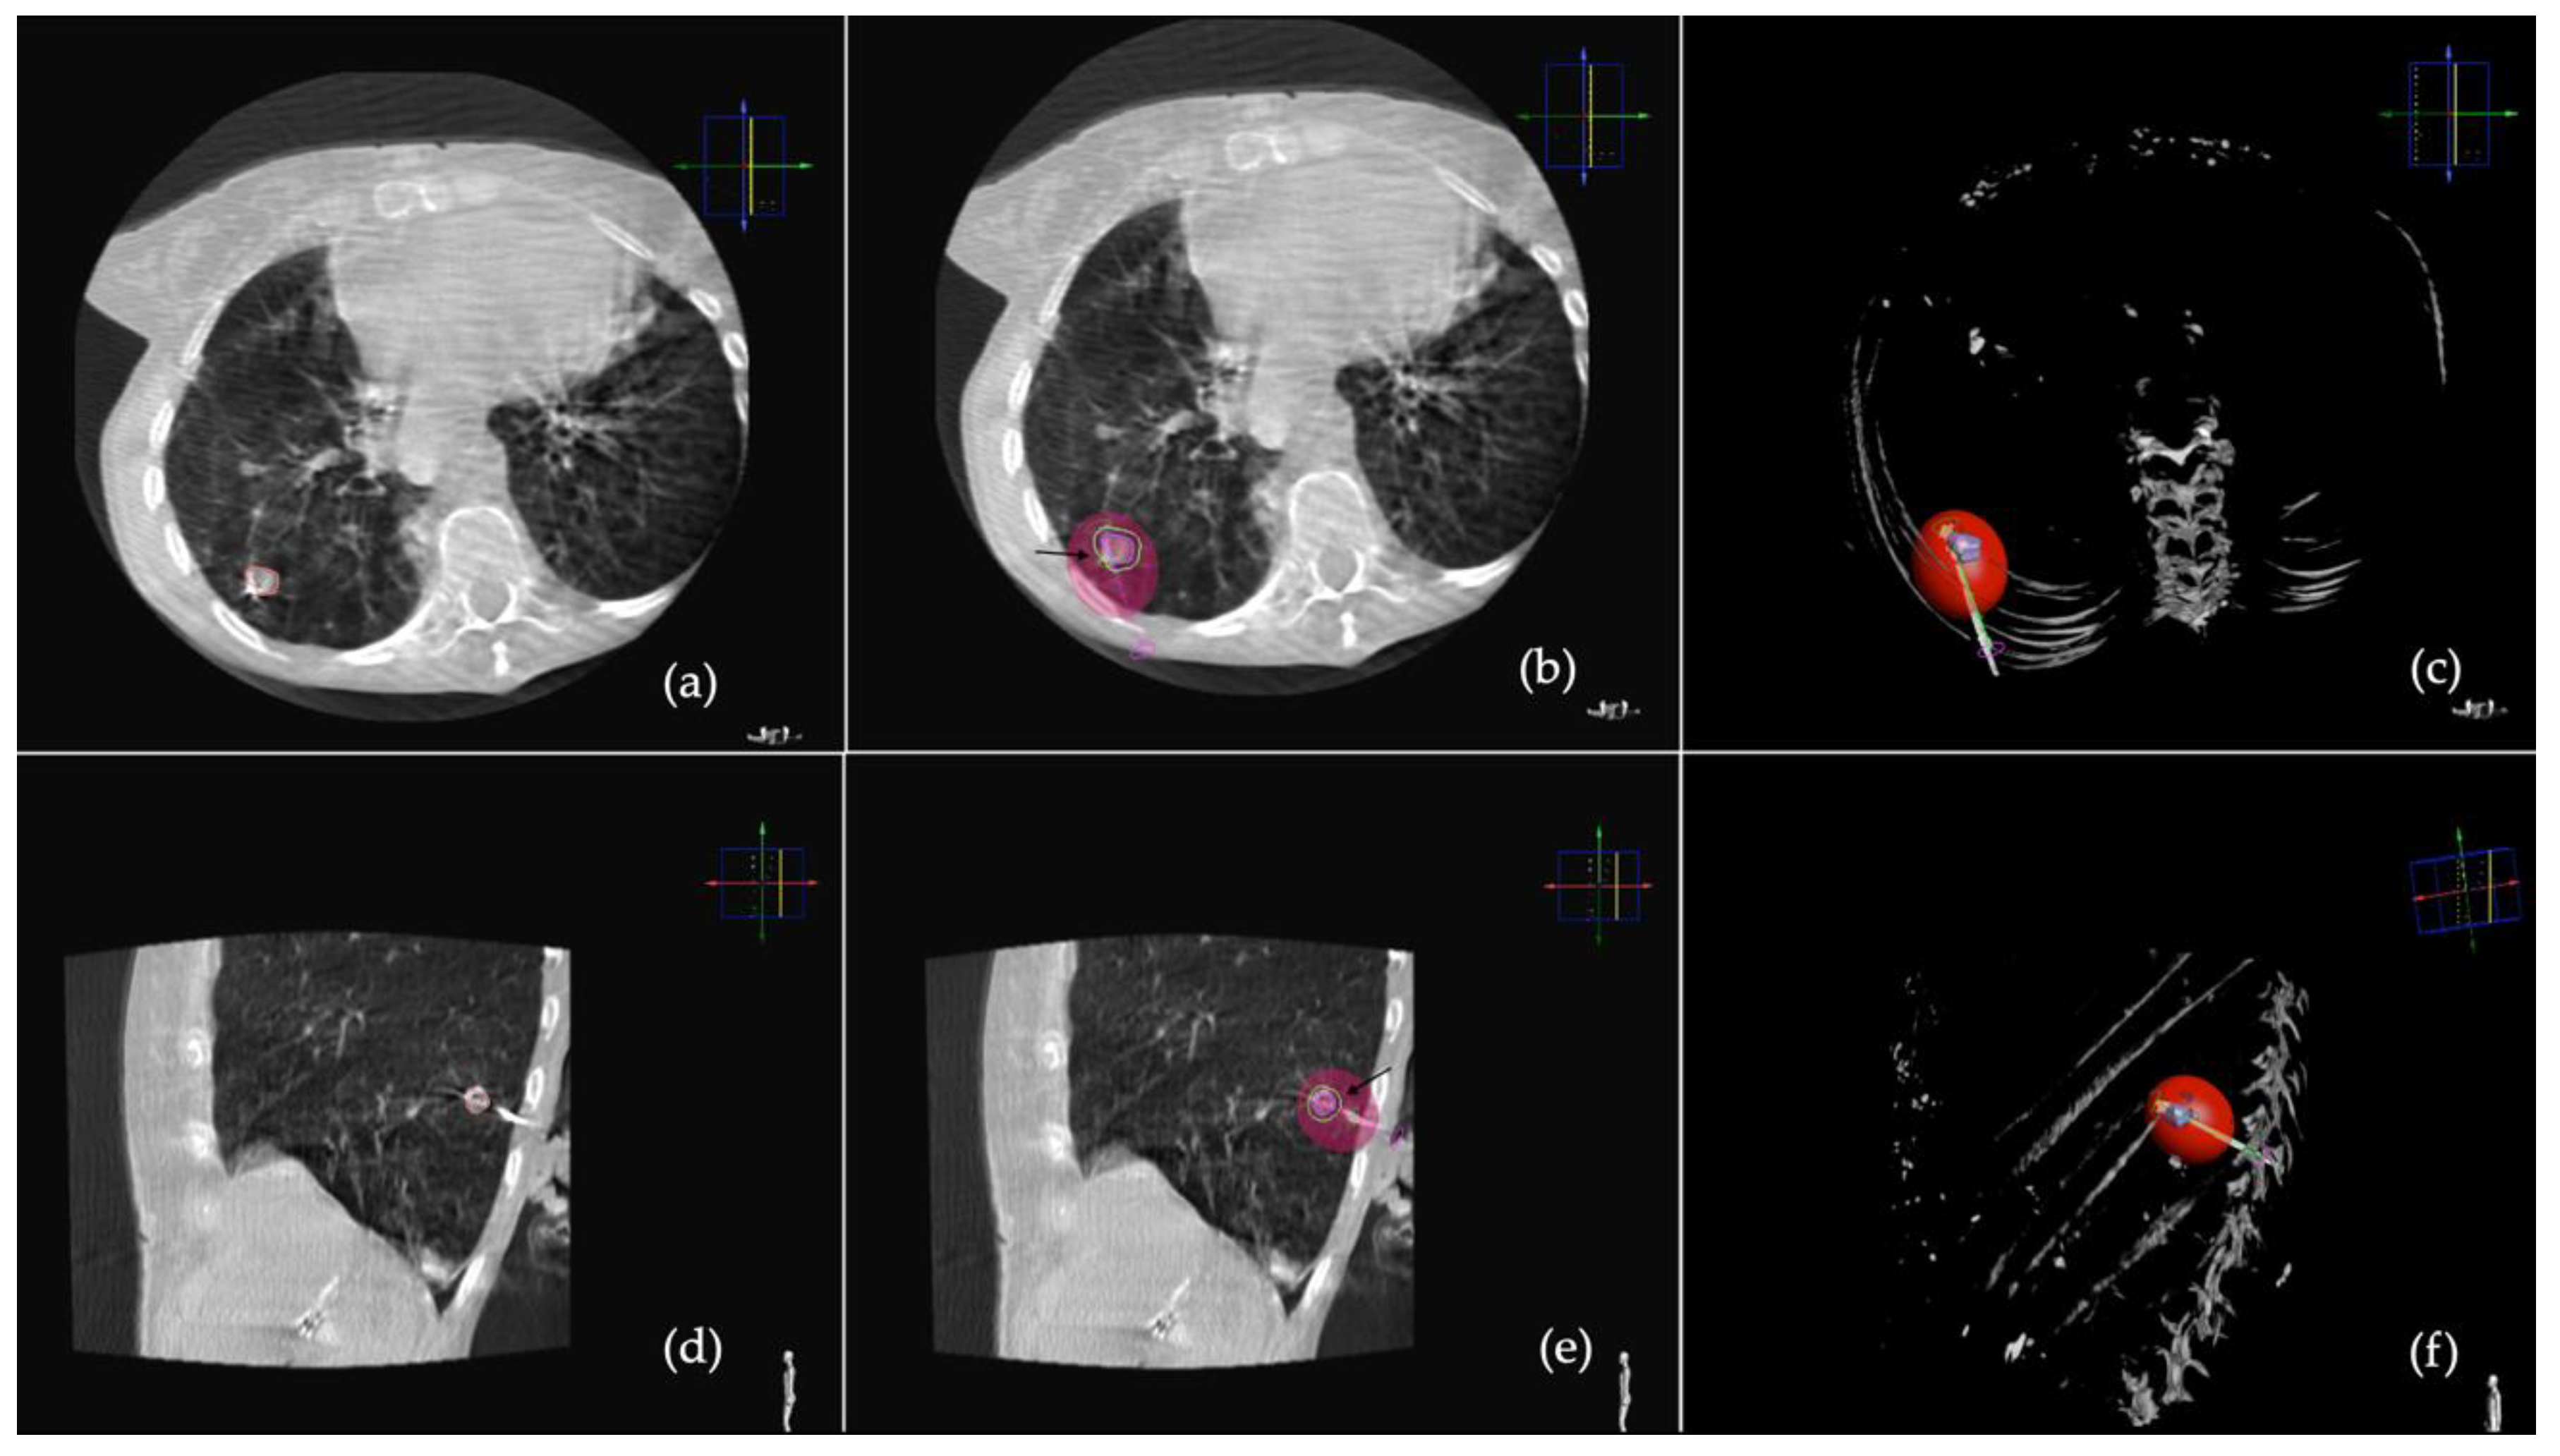

2.2. Procedure

2.3. CT Follow-Up